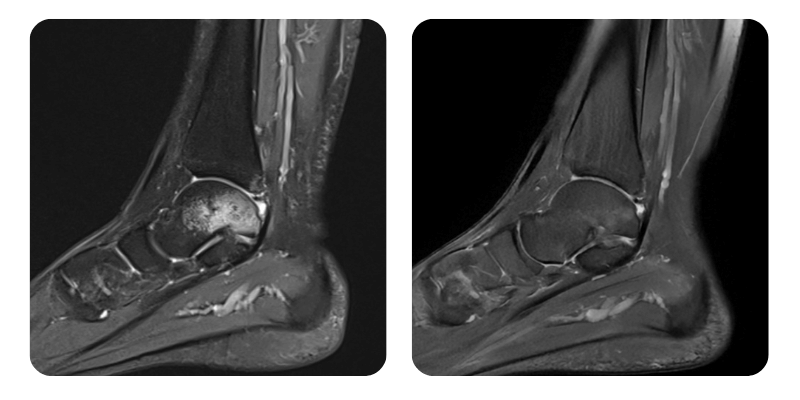

Előtte

Utána

B.A.A., 25 éves – Zúzódás utáni csontödéma a bal talus szintjén.

Diagnózis: Zúzódás utáni csontödéma a bal taluson, calcaneuson és cuboideumon, valamint a belső és külső bokák szintjén; bal elülső talo-fibuláris szalagruptúra; ödéma a hátsó talo-fibuláris szalagnál és a deltaszalag mély részén; ízületi folyadékgyülem.

Lefolyás: Az ödéma körülbelül 90%-kal csökkent.